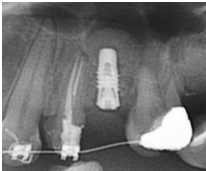

完成後大約半年至一年進行一次例行性追蹤檢查,並無特別問題。以下為96/08/13時的追蹤小片,可以見到當時三顆植體的骨高度並無顯著變化。但右下第一小臼齒此時發現有搖動度增加的情形,當時對該顆牙做了咬合調整,降低咬合功能負荷,希望能有所改善。

96/08/13

患者之後於96/11/08在右下第一小臼齒與植體間有膿胞產生,並於97/02/21確認右下第一小臼齒有根裂的情形,因此在97/02/29拔除此牙;經過將近半年後,於97/09/23放置一顆植體於此位置

97/02/21 確定根裂時拍的片子